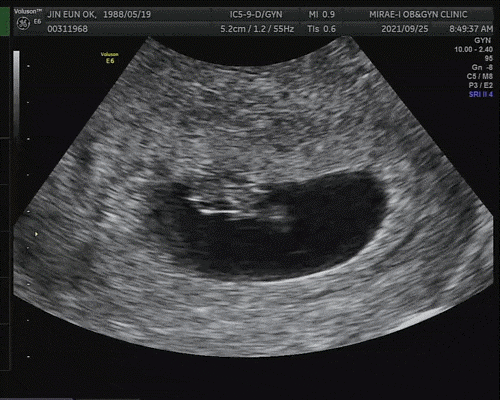

임신 7주 2일 심장 소리를 듣는다!

일단 저번보다 아기가 많이 컸다고 비춰주셨어요 아기의 크기는 1.1cm, 7주, 1일 정도로 예상 주수에 맞게 커진다고 합니다.

오른쪽 동그란 거 노른자 같아?동그란 반지 모양 잘 나왔어요 ㅋㅋ

그리고 빛나는 게 아기키라키라 하는 걸 보여줬어요 (웃음)